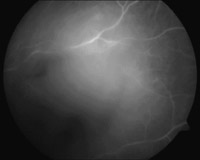

La ecografía ocular descartó la presencia de lesiones regmatógenas ocultas por la hemorragia; en la angiografía ocular (

Figura 2) no se hallo tampoco ningún dato relevante, la analítica y exploración general fueron completamente normales.

Figura 2. Angiograma normal, donde se evidencian restos del hemovitreo en reabsorción